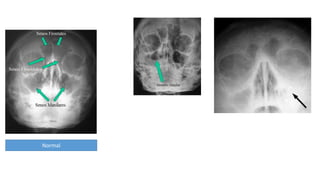

Radiografía de senos paranasales

• Presencia de un nivel hidroaéreo o la opacificación completa de una o ambas

cavidades sinusales.

• El nivel hidroaéreo es poco común en el niño menor de cinco años con

rinosinusitis aguda

Poryecciones

Waters

Caldwell

Lateral

Submentoniana

Visualizar seno maxilar y

estructuras intranasales

Observar senos

frontoetmoideos

Observar Seno esfenoidal, evaluar la integridad de pared

posterior de senos maxilar y frontal

Observar celdillas etmoideas posteriores

Proyección Waters

Proyección Cadwell

Proyección submentoniana

Proyección lateral

Normal